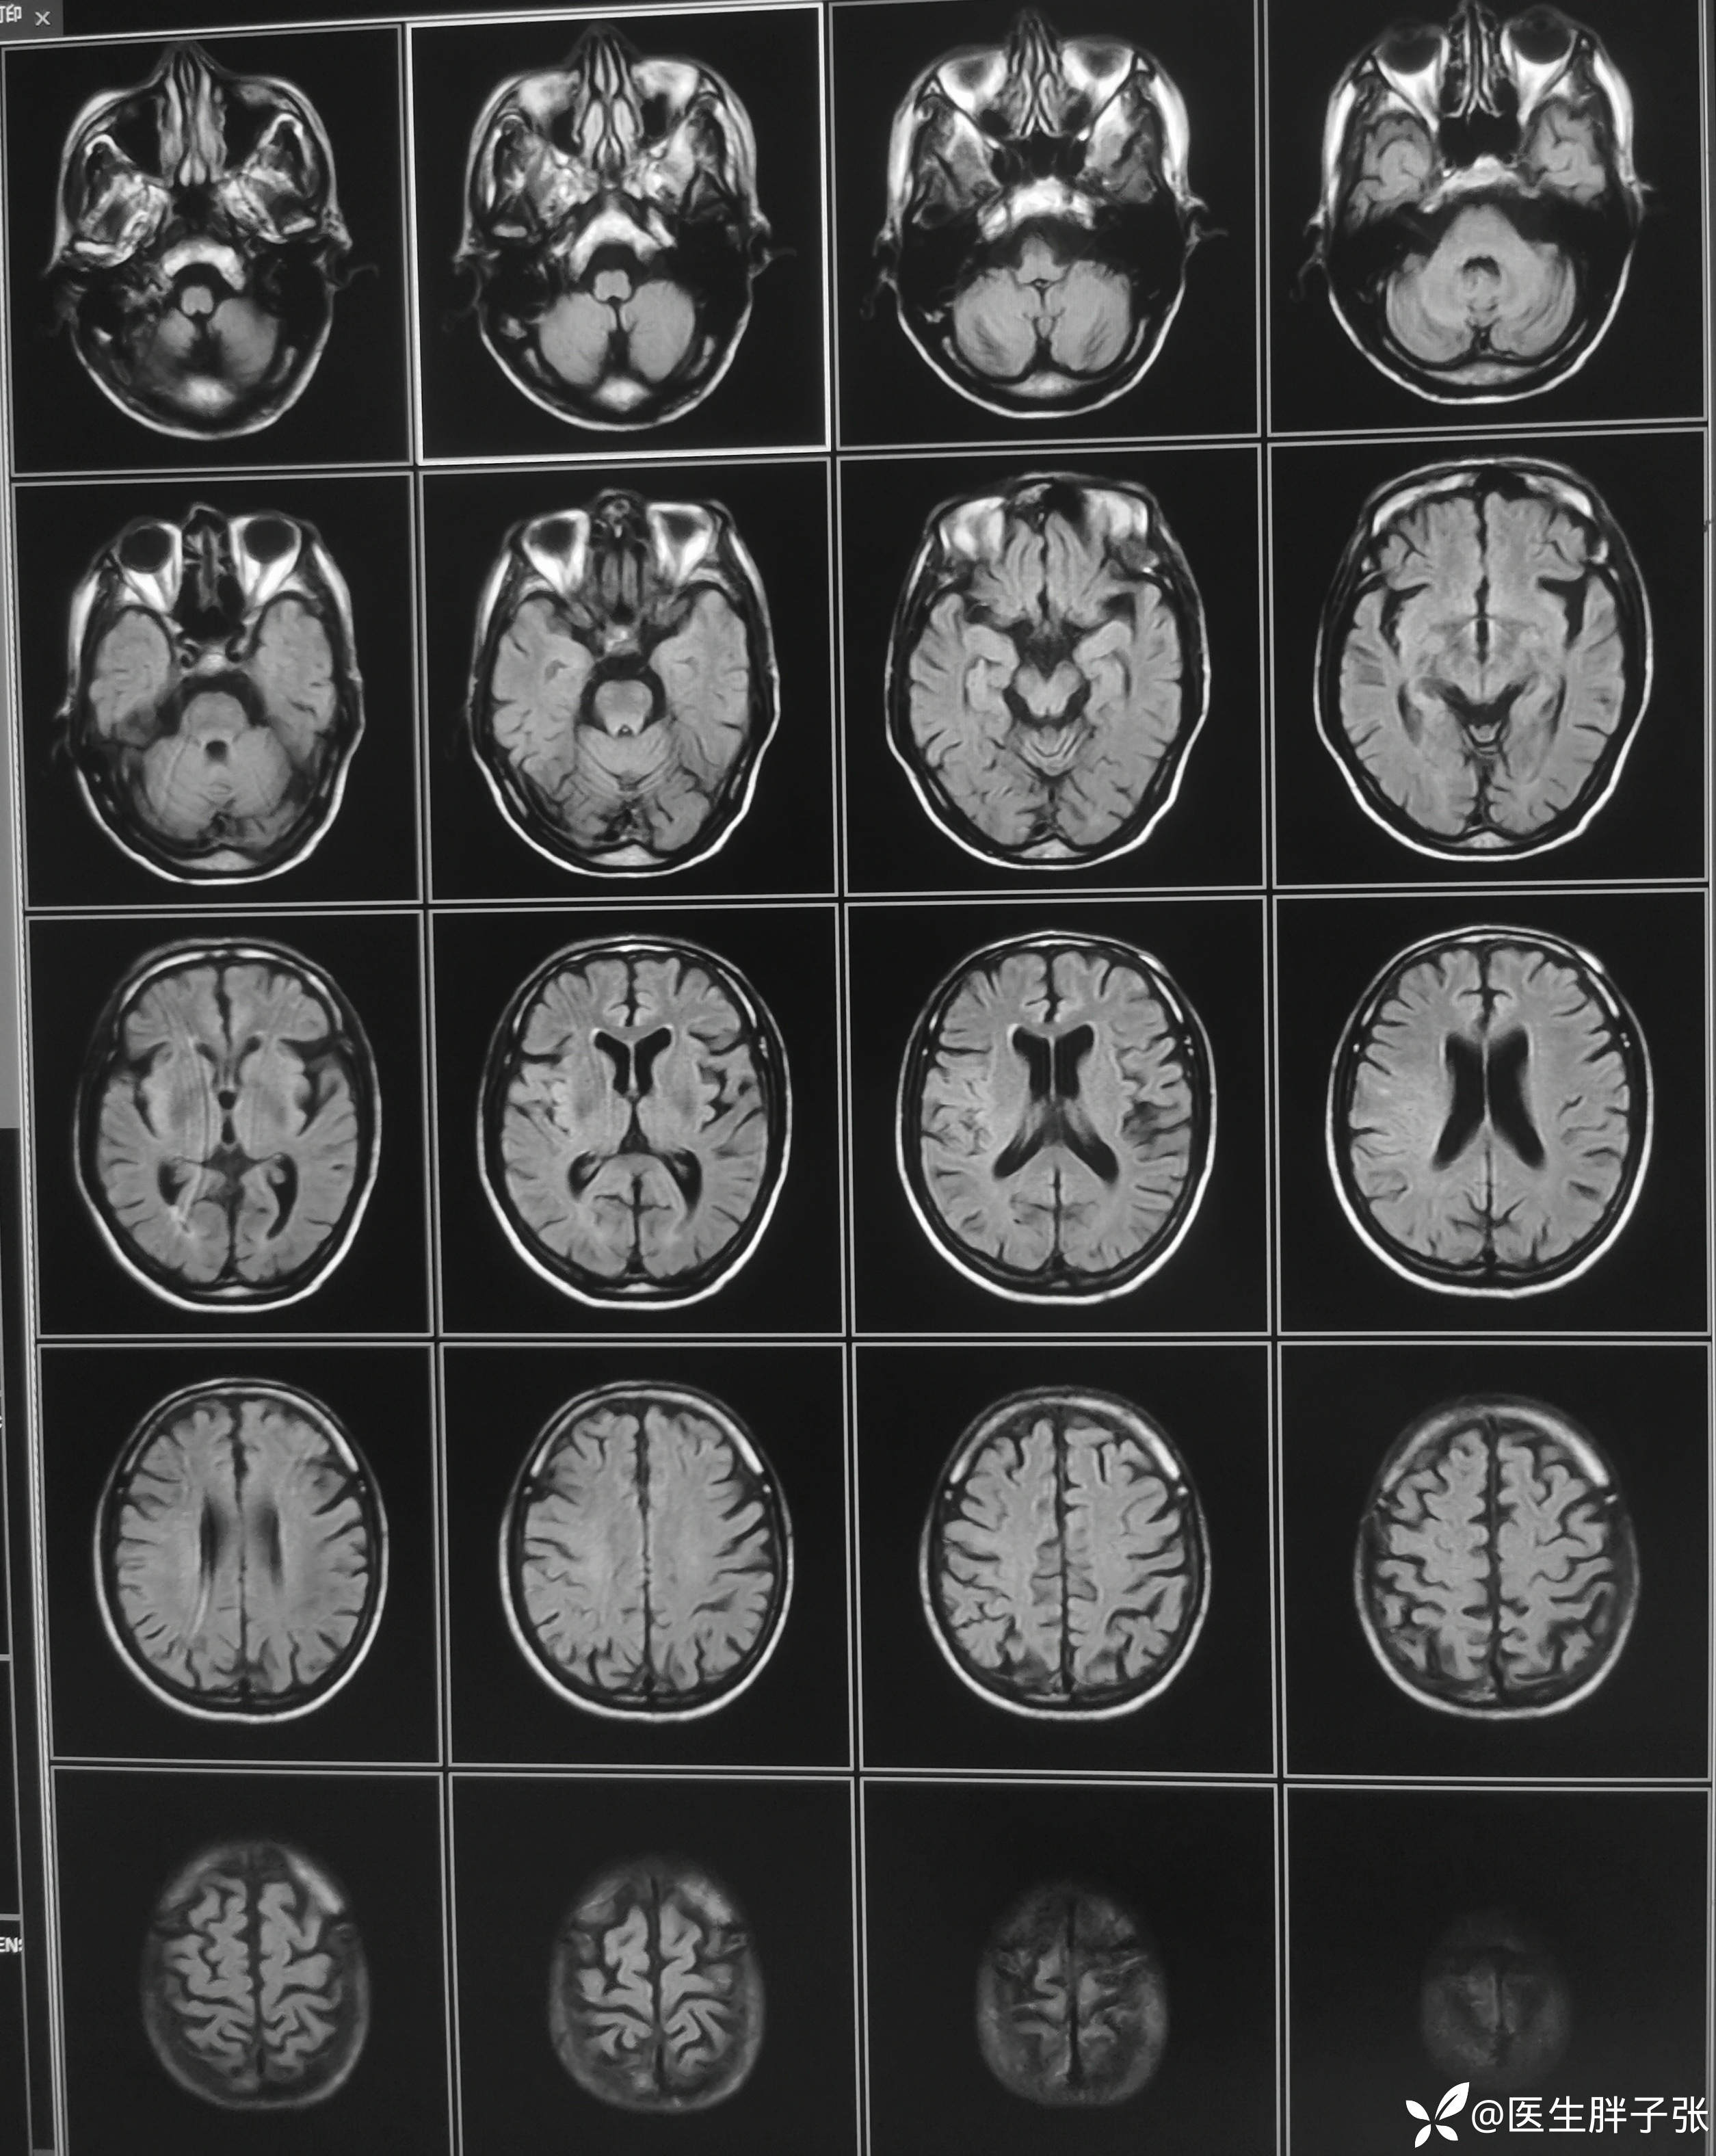

颅脑MR:右侧颞叶新近梗死灶;老年性脑改变;右侧大脑中动脉部分M2段及以远未见显示,建议头颈部CTA检查。

患者为醒后卒中患者,幸运的是恰好晨起交班的时候来院,恰好能查核磁,核磁提示存在DWI-FLAIR错配